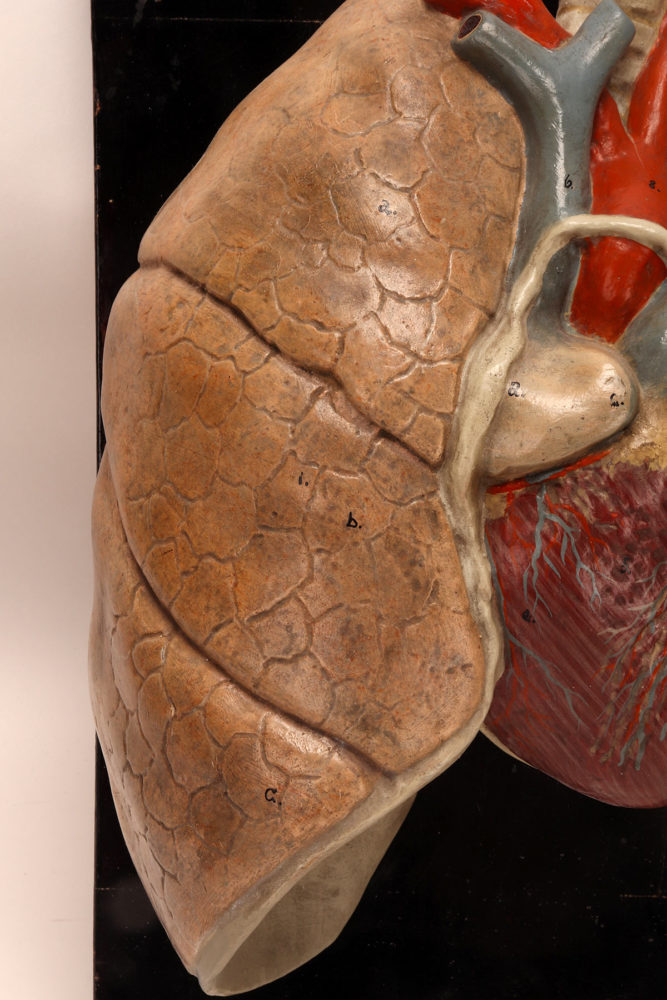

Anatomical model for class of the lungs and heart, Germany 1920.

Rare anatomical model for class, depicting human lungs and heart, made out of painted plaster, mounted on a black fruit wooden base. By Louis M. Meusel, Germany circa 1920.